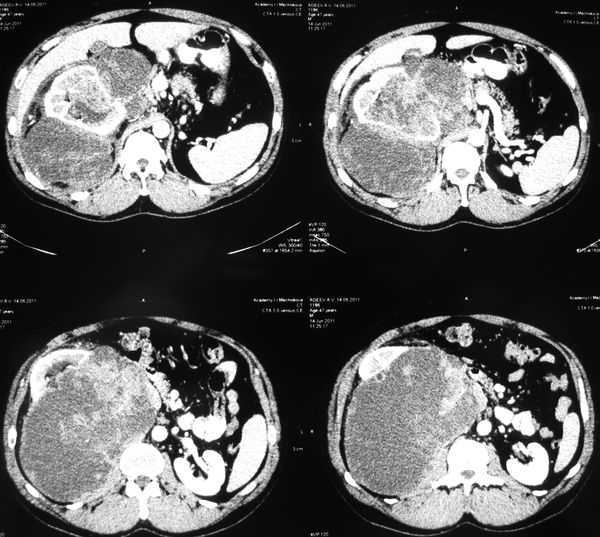

Огромная опухоль правой почки

Гигантская опухоль правой почки. Экстримальная нефрэктомия.